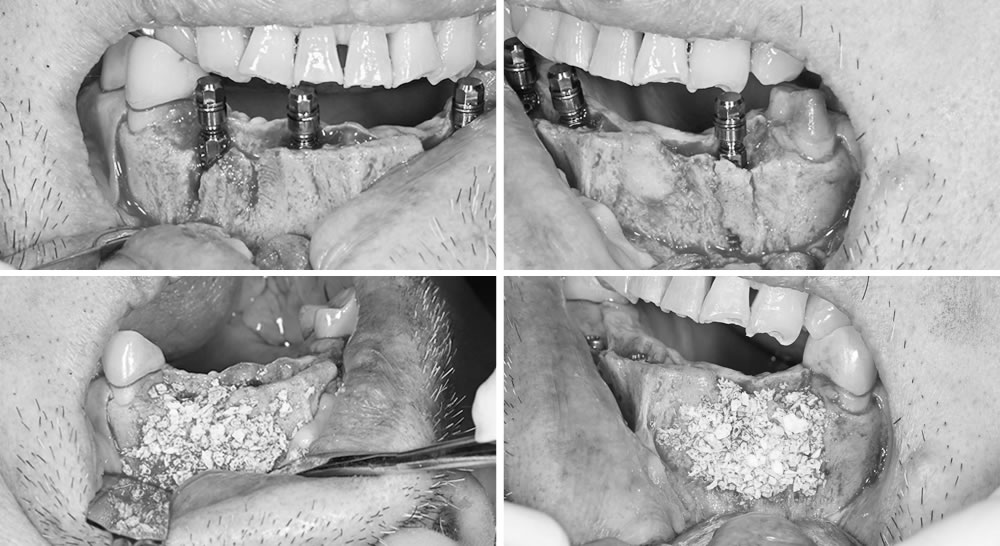

歯肉を剥離し、インプラントを埋入した状態です。設計されたサージカルガイドとズレが生じないよう、精密な処置を行いました。

唇側の骨が不足していたため、インプラントの埋入と同時に人工骨を用いて骨補填を行っています。